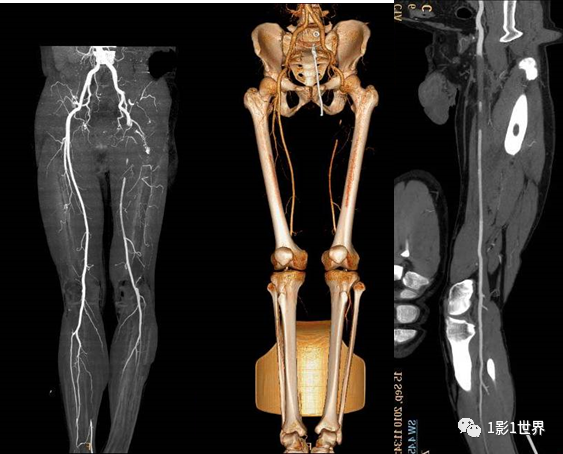

糖尿病20年,左下肢疼痛、间歇性跛行5年,静息痛1年,加重并变黑2个月。住院后下肢CTA示左下肢血管广泛不光滑,节段性轻度狭窄,其中最严重的是左侧股浅动脉中段重度狭窄(约90%),长度约8cm。

介入科DSA血管造影,确认了CTA诊断,同时行球囊扩张,支架置入术,再次造影,股动脉再通,远端血流较好。